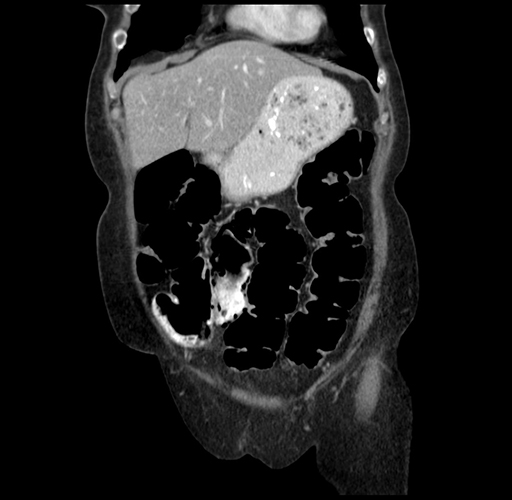

Pre-Chemo: Axial Venous

Pre-Chemo: Coronal Venous